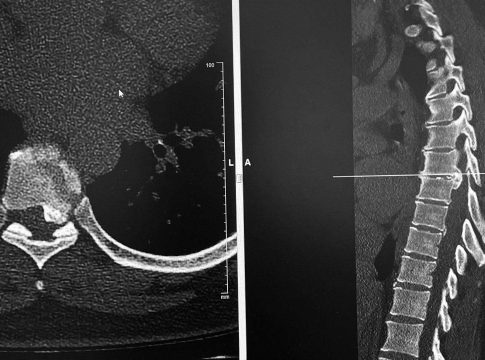

Los discos dorsales son tejidos semejantes a un cojín esponjoso que se encuentran entre las vértebras de la columna. Las hernias aparecen cuando uno de los discos sobresale de entre las vértebras, presionando los nervios y la médula, lo que produce dolor y otros síntomas como la sensación de hormigueo, dependiendo del lugar en el que se originen.

Es común que con la edad, el material gelatinoso que amortigua los discos se debilite y desaparezca, posibilitando movimientos que los desvíe de su posición original, produciendo de esta manera una hernia. Cuando el disco llega a presionar la médula o algún otro nervio importante, es posible que el paciente presente sensación de adormecimiento en las extremidades y, en casos más graves, debilidad en las extremidades o dificultad para el movimiento.